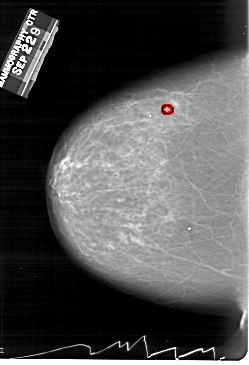

FILE: A_1260_1.LEFT_CC.OVERLAY

TOTAL_ABNORMALITIES 1

ABNORMALITY 1

LESION_TYPE MASS SHAPE ARCHITECTURAL_DISTORTION MARGINS ILL_DEFINED

ASSESSMENT 4

SUBTLETY 2

PATHOLOGY MALIGNANT

TOTAL_OUTLINES 1

BOUNDARY